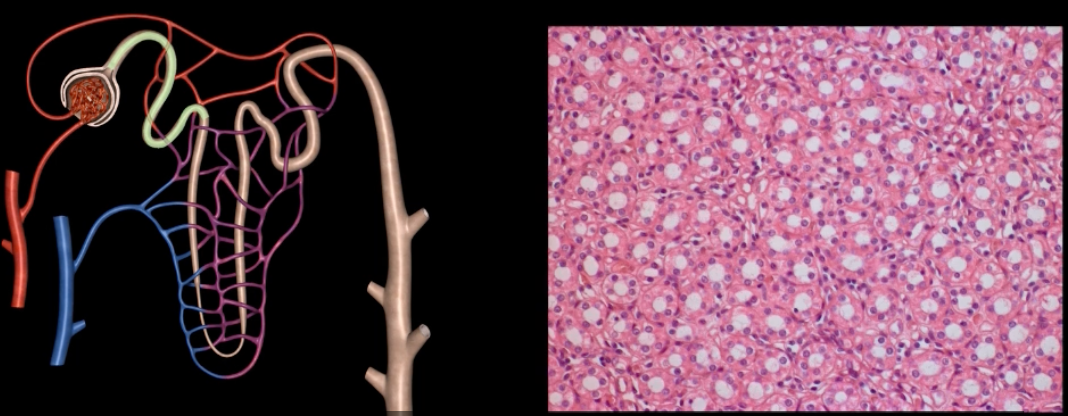

yellow: cortical nephron

blue: juxtamedullary nephron

yellow:

blue:

afferent arteriole

yellow

glomerulus

green

efferent arteriole

purple

orange: peritubular capillaries

green: vasa recta

efferent arteriole give rise to orange and green

pink: podocyte

purple: pedicels